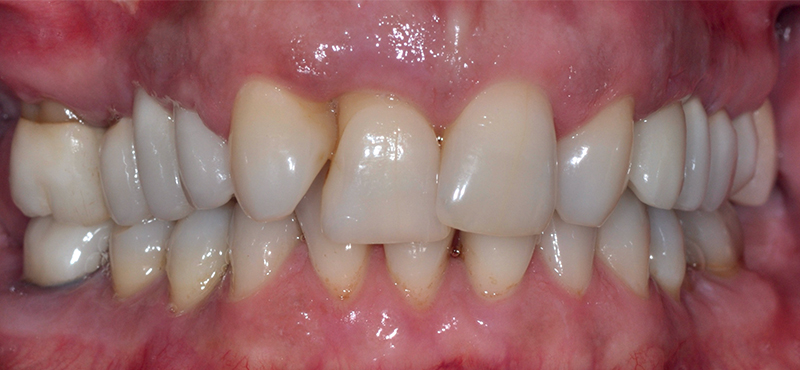

Fig. 18 (caso 4) - Situazione clinica iniziale

Caso 4: Una paziente, fumatrice, con parodontite avanzata e numerose cisti periapicali in entrambe le regioni superiori posteriori, presentava perimplantite terminale a carico degli impianti in titanio pre-esistenti, grave mobilità dei denti e marcata perdita ossea in tutte le regioni del mascellare. Inoltre, si osservava uno spostamento della linea mediana di ca. 4 mm, con denti mancanti (12 e 22). La maggior parte dell'osso alveolare buccale dei denti 11 e 21 era già andata perduta, e la linea del sorriso alta del paziente presentava sfide estetiche. Per compensare lo spostamento della linea mediana e creare una dentatura regolare da 16-26, la paziente optava per il posizionamento immediato di impianti a carico immediato (attraverso riabilitazione con protesi provvisoria a lungo termine), per un totale di 10 fixtures nell'arcata superiore. Gli impianti venivano attentamente monitorati, così come le condizioni parodontali della paziente. Dopo 6 mesi gli impianti venivano finalmente preparati e dotati di corone in ceramica definitive. Nello stesso periodo la paziente acconsentiva anche all’inserimento di un impianto nella regione dei molari inferiori, che portava ad una completa riabilitazione orale. Subito dopo il primo intervento chirurgico (rimozione di tutti i denti infiammati e degli impianti in titanio nel mascellare superiore, ed inserimento immediato di 10 impianti in ceramica a carico immediato), lo stato di salute generale del paziente migliorava notevolmente, come chiaramente veniva confermato 7 anni dopo (Fig. 18-21).